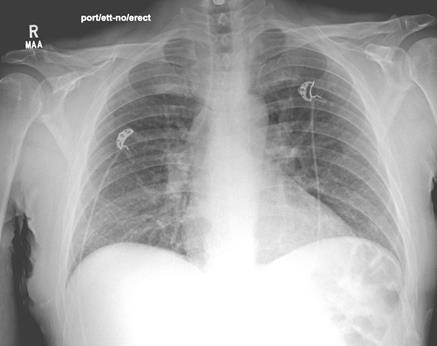

Infectious disease recommended broad-spectrum antibiotic coverage with vancomycin, clindamycin, piperacillin-tazobactam, and levofloxacin due to concern for Aeromonas species from freshwater exposure. Unexpectedly on postop day 3, the patient started complaining of respiratory discomfort and overall body swelling. The patient had new-onset dyspnea, hypoxemia, hydrocele, and edema, resulting in placement on a BiPAP machine. Laboratory investigation revealed leukocytosis, with a white blood cell count of 19.1×109/L (normal range 4×109/L to 11×109/L) with normal peripheral absolute eosinophil count of 0×109/L, and lactate level of 0.9 mmol/L. His arterial blood gas pH was 7.48 (normal pH 7.35 to 7.45), partial pressure of O2 77 mmHg (normal greater than 70-125 mmHg), partial pressure of carbon dioxide 26 mmHg (normal 35 mmHg to 45 mmHg), and calculated bicarbonate of 22 mmol/L (normal 23 mmol/L to 28 mmol/L). A repeat chest X-ray (see image to left) revealed new onset of pulmonary edema. A new computed tomography (CT) of the chest (see image below) showed diffuse ground-glass opacities with small pleural effusions and diffuse subpleural sparing, attributable to pulmonary edema with possible pneumonitis.